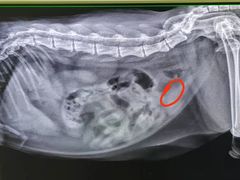

• 瑞派动物医院·猫专科·至诚(江南中分院)

• -瑞派动物医院·猫专科·至诚(江南中分院)

Nikodema | 21-03-08